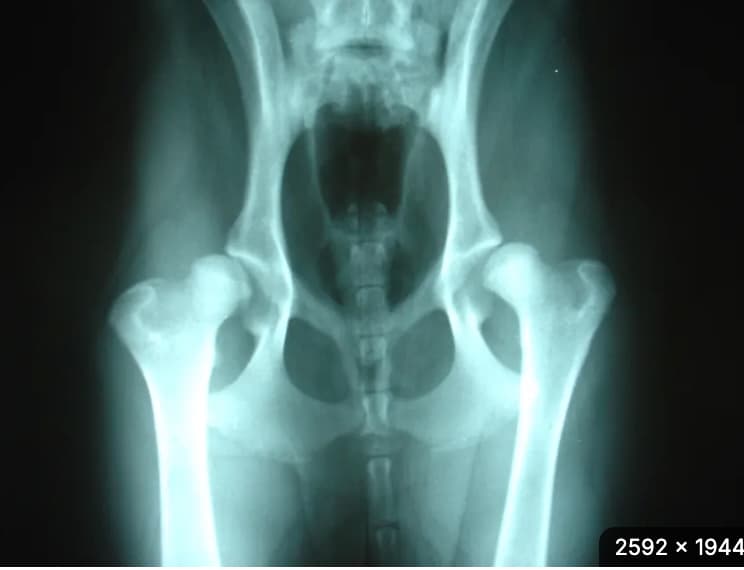

Hip Dysplasia

Randi I. Krontveit’s doctoral research has studied the incidence of HD in four breeds of dog in Norway and examined factors in the environment where the dogs grew up that can have an affect on the number of cases. HD is a genetic disease which also occurs in several other species. Dogs are not born with HD, but genetically disposed puppies can develop varying degrees of HD. The degree of HD has an affect on when the dogs show symptoms and on how long they live.